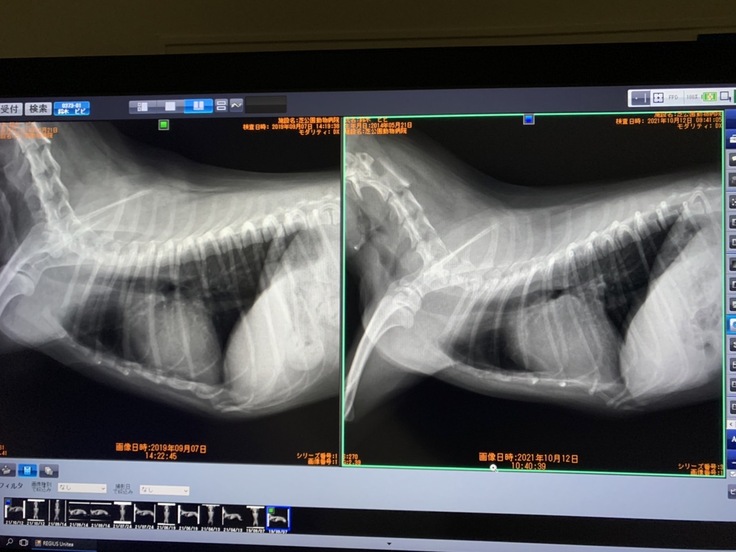

↑左)正常だった頃の心臓 右)現在の大きくなった心臓

↑病状悪化による度重なる通院と検査